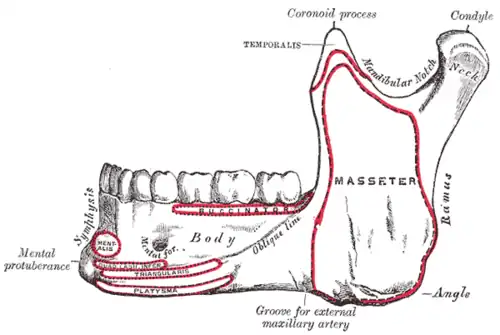

Mandible, outer surface, side view

Mandible, outer surface, side view -